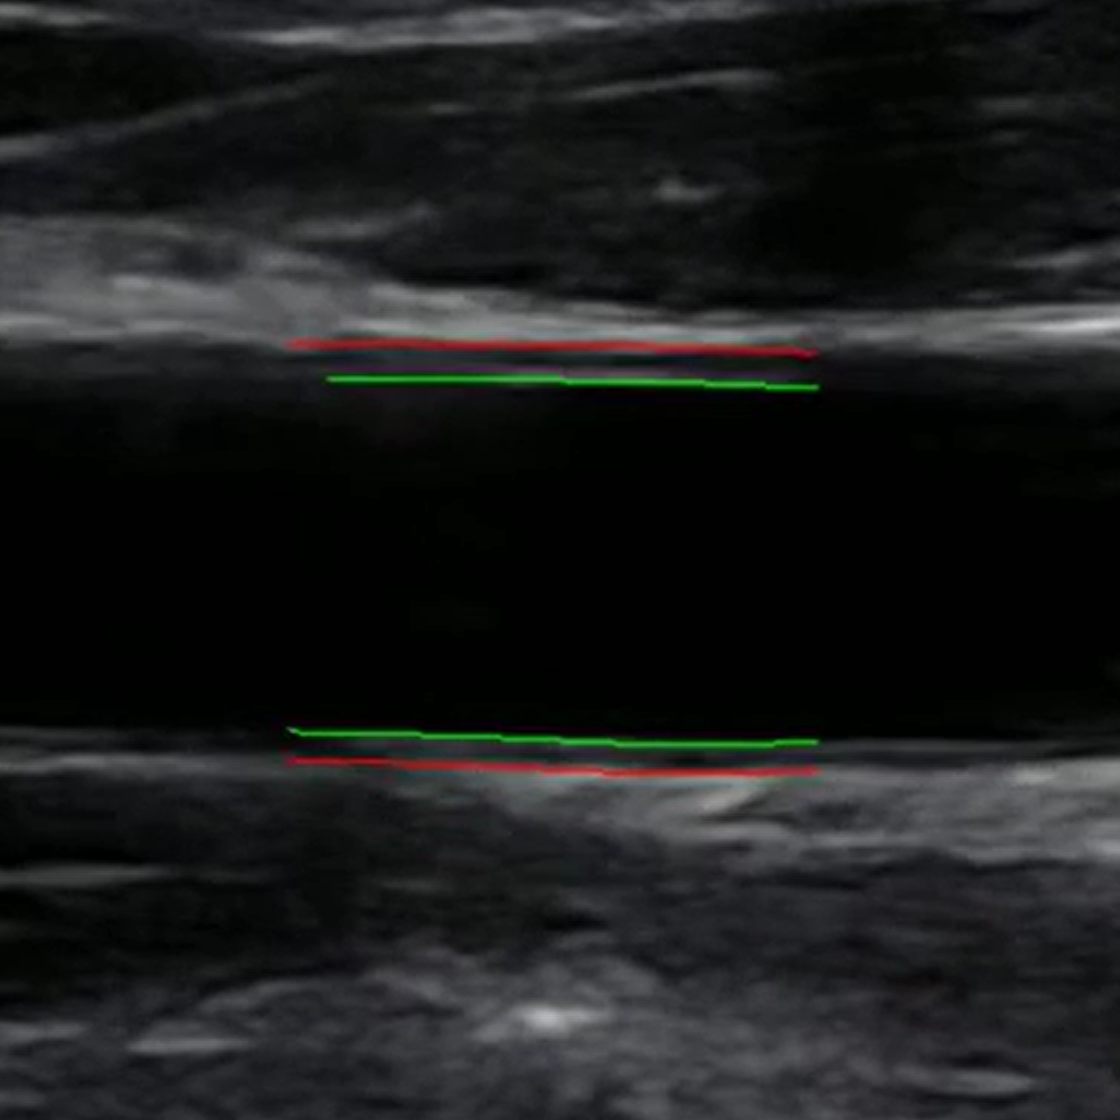

MAUI (Measurements from Arterial Ultrasound Imaging) overcomes these challenges by automating the analysis of ultrasound videos. Utilizing state-of-the-art computer vision algorithms, MAUI accurately detects and tracks arterial walls, enabling researchers to:

• Measure intima-to-intima diameter, intima-media thickness (IMT), and blood velocity.

• Obtain reliable, continuous diameter measurements throughout the cardiac cycle.